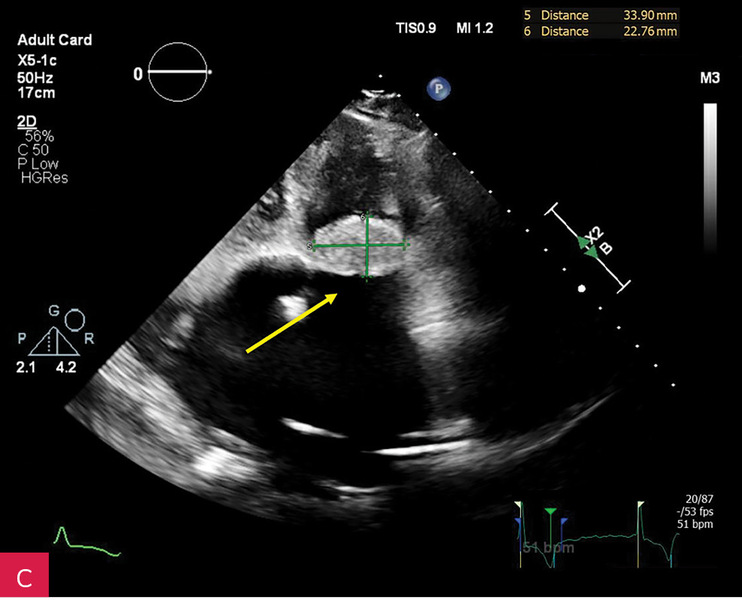

Rycina 3A-C. Badanie echokardiograficzne przezklatkowe (TTE) w osi krótkiej przymostkowej na różnych poziomach – płatków zastawki mitralnej (A), strun ścięgnistych (B) i mięśni brodawkowatych (C) – obrazuje owalną zmianę guzowatą, o dużych rozmiarach i nierównej echogeniczności, z widocznym wzmocnieniem brzeżnym